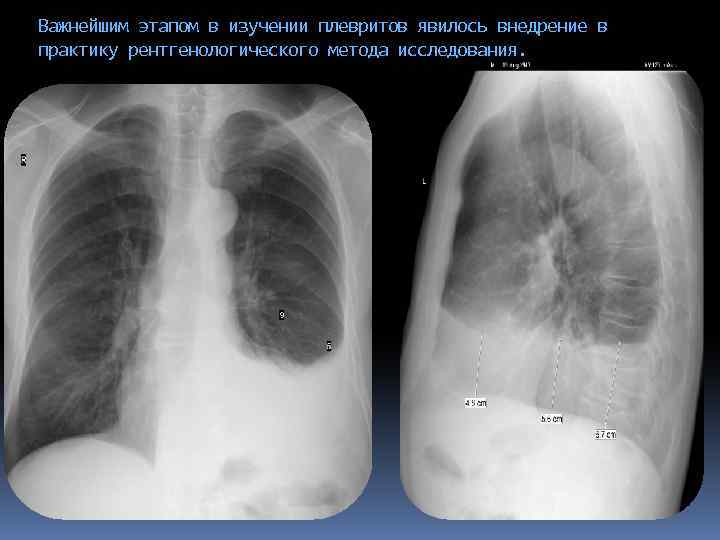

Важнейшим этапом в изучении плевритов явилось внедрение в практику рентгенологического метода исследования.